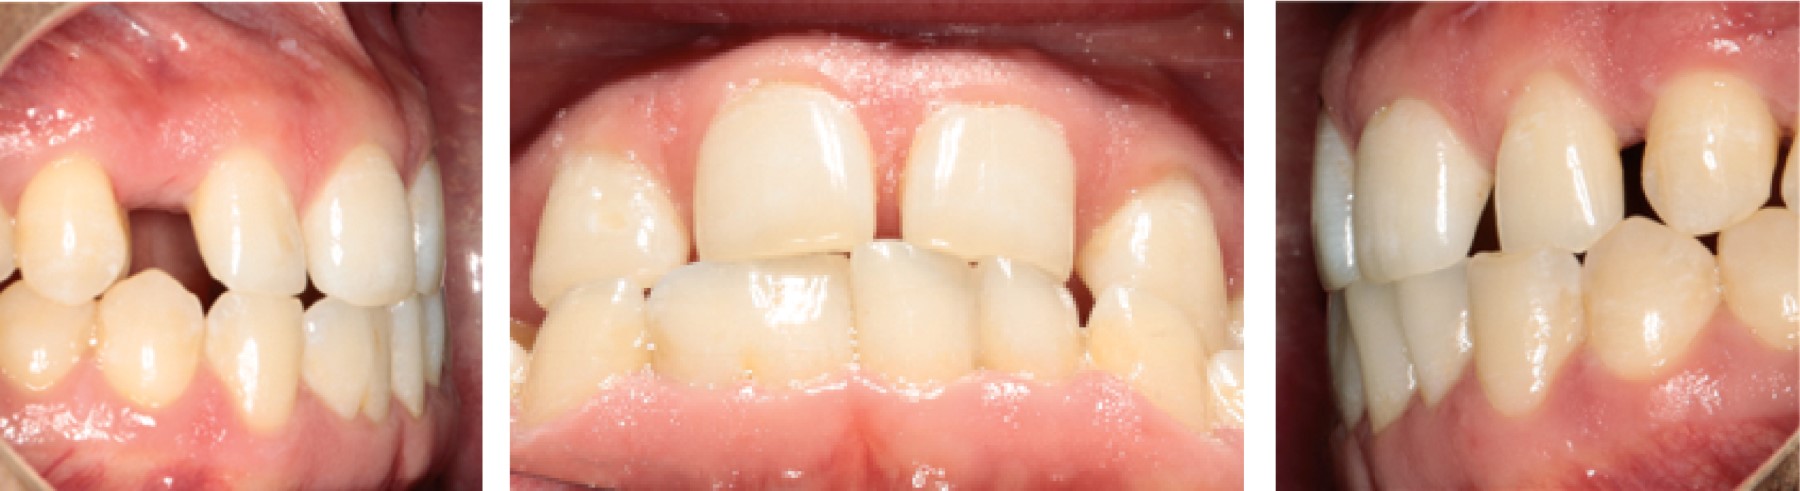

Al inicio, se tomaron registros clínicos para su análisis diagnóstico como fotografías de estudio extraorales e intraorales (Figura 1), modelos montados en articulador Panadent (PANADENT®, CA, EUA), radiografías, exploración física de articulación temporomandibular y exploración clínica para realizar análisis ortodóncico dental. Una vez realizada la toma de registros se realizaron las siguientes observaciones.

Aspectos dentoalveolares: se consideró la discrepancia oseodentaria positiva en arcada superior de 7 mm, discrepancia oseodentaria negativa en arcada inferior de -7.9 mm, proinclinación de incisivos centrales inferiores, proinclinación de incisivos centrales superiores, línea media dental inferior desviada 3 mm hacia la derecha respecto a línea media dental superior, overbite incisivo 1.5 mm, curva de Spee de 1 mm, relación molar clase III bilateral, relación incisiva clase III, overjet incisivo 0.5 mm (Figura 3), desgaste dental, ausencia de caninos y también condiciones morfológicas específicas, como la fusión de los órganos dentales 41 y 42 a nivel coronal, así como geminación en órgano dental 27.

Figura 1